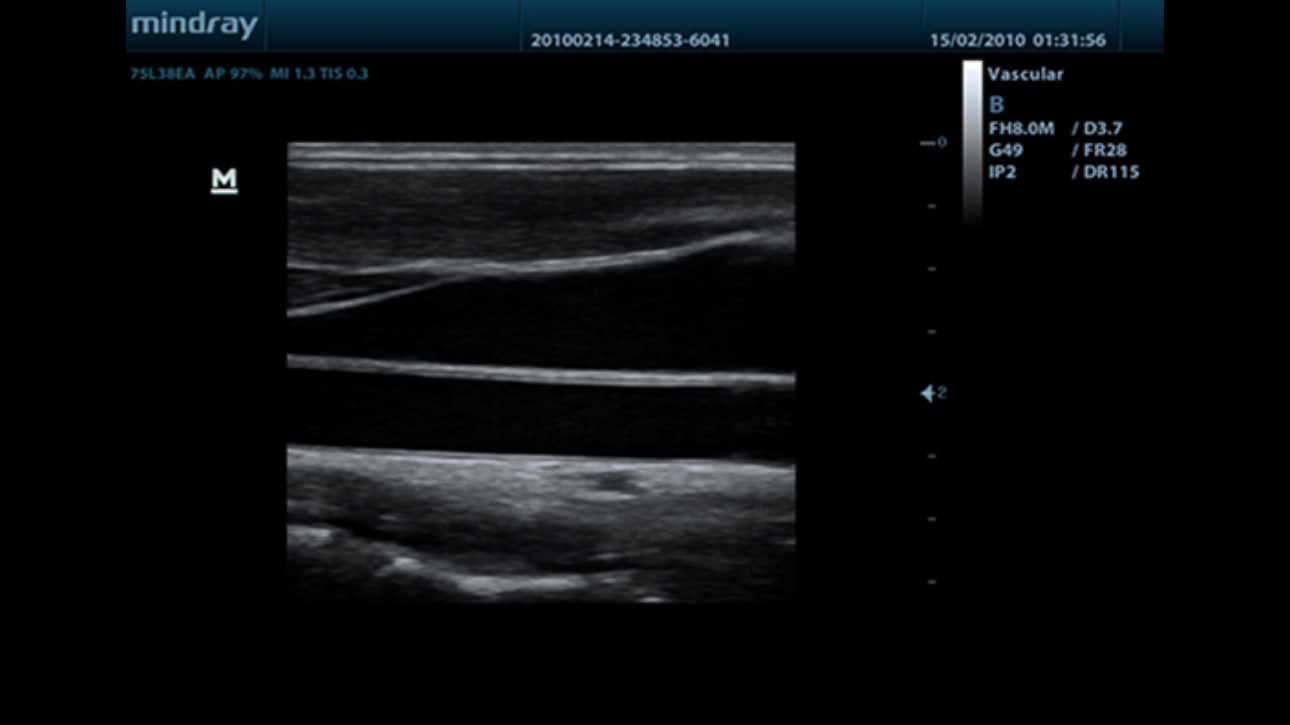

Auto IMT (Intima-Media Thickness)

Auto measurement of anterior and posterior wall thickness providing accurate carotid status